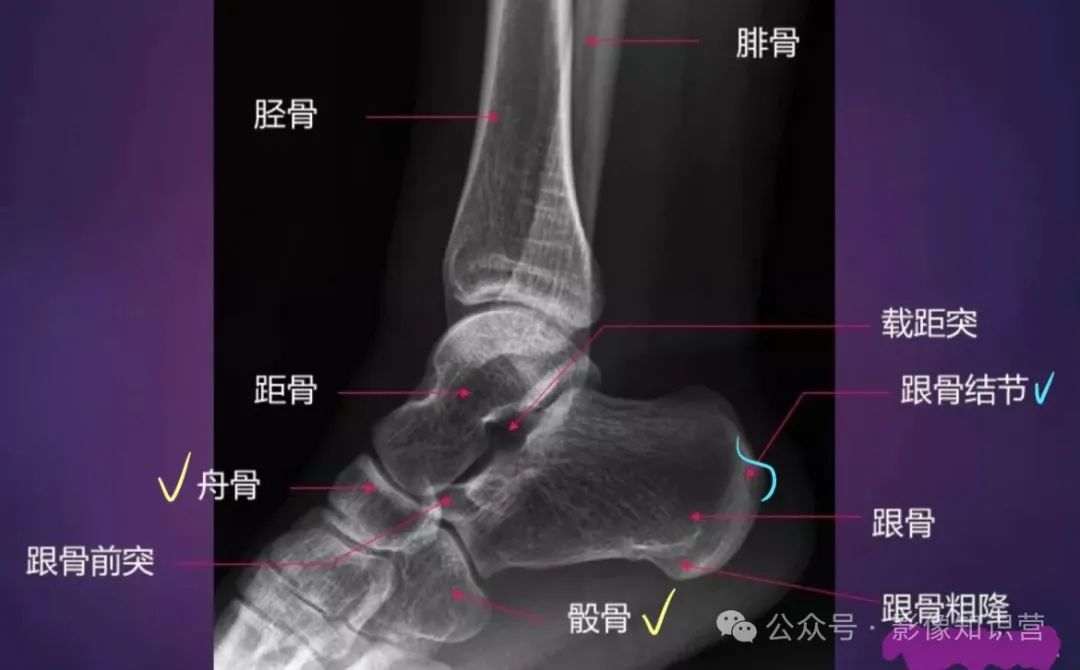

踝关节

骨骼组成:胫骨远端(内踝)、腓骨远端(外踝)、距骨。

影像特征:X线正侧位:观察踝穴(距骨与内外踝的匹配)及下胫腓联合宽度(正常<6mm)

足部

骨骼组成:跗骨(7块:距骨、跟骨、足舟骨、骰骨、3块楔骨)。跖骨(5块)、趾骨(14块)。

影像要点:

跟骨骨折需评估Böhler角(正常20°-40°),角度减小提示压缩性骨折。